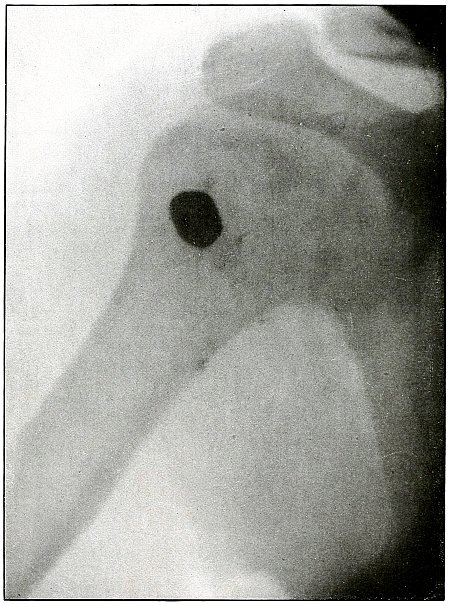

Rifle—Plate 10.

UPPER EXTREMITY.

Gunshot Fracture of the Left Humerus,

with Lodgment of the Missile.

Wound of entrance, anterior surface of upper third of the arm.

Wound of exit, none.

The shadow of the missile shows by its distinct outline and normal

diameter at the tip that the missile lies on the side near the plate;

the shortened length of the projectile indicates that the long axis

lay in an acute angle with a perpendicular to the plate.

The irregular outline of the base of the shadow and the fact of

lodgment shows that the missile was deformed and that it was

incidentally retarded in velocity by ricochet, so that its penetrating

force was not sufficient to carry it through the arm.

The fragments of bone are large and the wound is of the same character

as might have resulted from a shrapnel ball, for the normal ballistic

conditions of the latter simulate the conditions that produced the wound.

The drainage tubes seen in the plate indicate infection.

The conventional treatment in such cases is drainage and other

management of the infection without formal search for the projectile.

Results should be favorable.